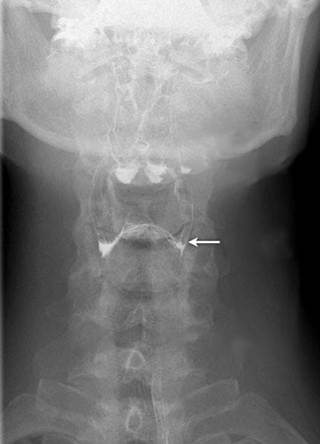

The persistence of which of the following arch arteries is responsible for the congenital anomaly marked in the image given below?

Options:

- 6th left pharyngeal arch artery

- 6th right pharyngeal arch artery

- 4th left pharyngeal arch artery

- 4th right pharyngeal arch artery

Correct Answer: A) 6th left pharyngeal arch artery